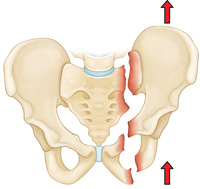

Vertical shear fracture. In this fracture, one half of the pelvis shifts upward.

Unstable fracture. In this type of fracture, there are usually two or more breaks in the pelvic ring and the ends of the broken bones do not line up correctly (displacement). This type of fracture is more likely to occur due to a high-energy event. Unstable pelvic fracture patterns include: